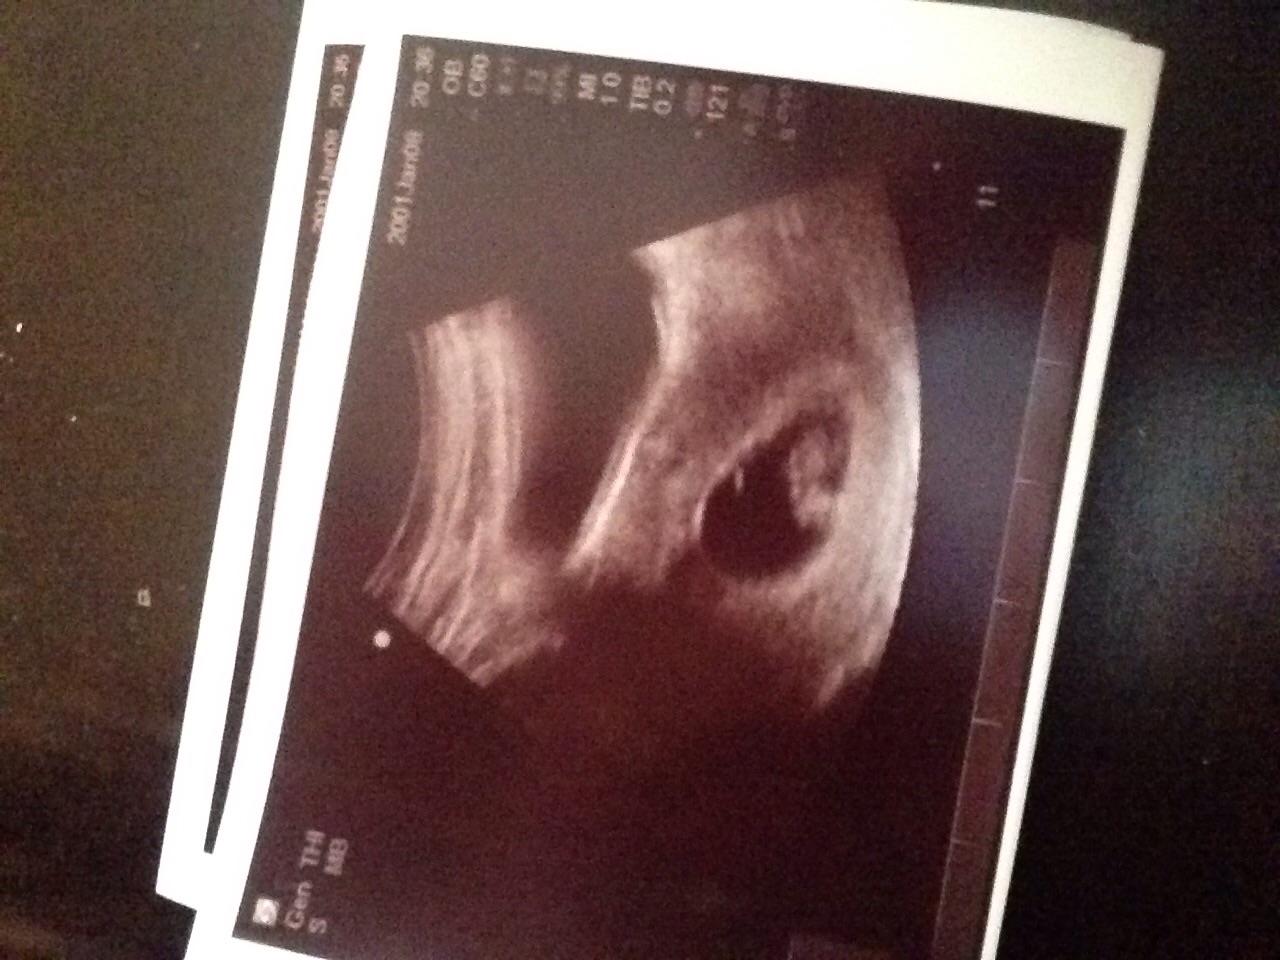

Quick scan done at 11weeks 3 days. FTM. Can't believe how big our baby has gotten from my 7week scan! (There were some concerns so I have gotten a couple of scans)